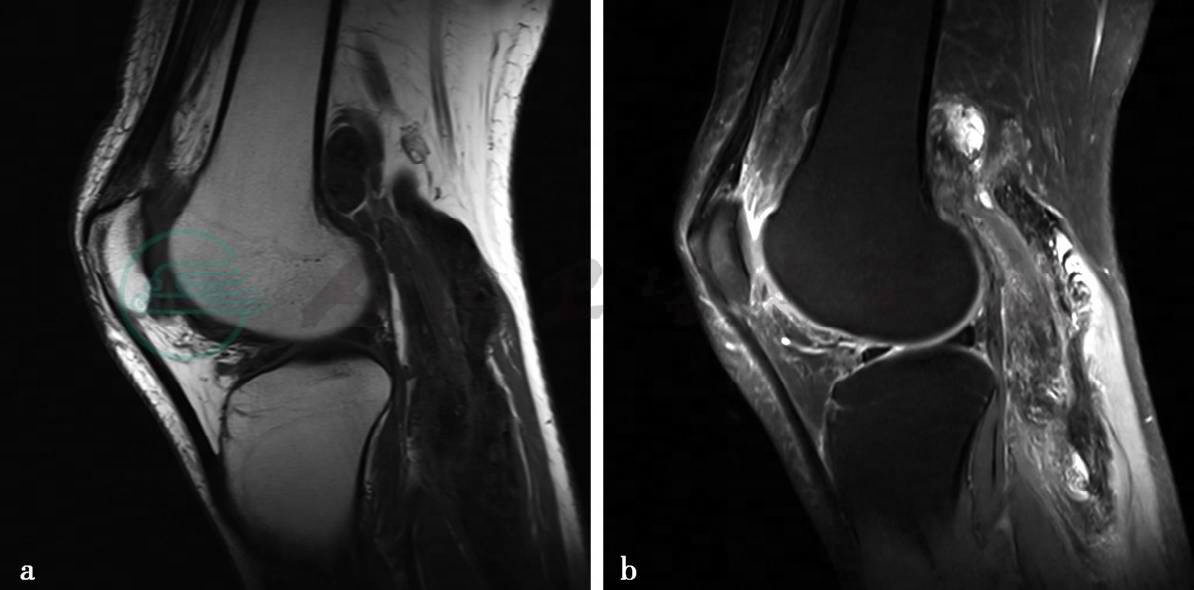

图1 图1a~c,MRI平扫示左膝关节前方髌下关节囊内可见一类圆形占位病变,病灶边缘较清楚,大小约2.3cm× 1.5cm。图1a,病灶在T1WI上呈低信号。图1b,在T2WI脂肪抑制像上呈稍高信号,边界清楚。关节囊内有较多液体信号影,并包绕上述占位病变。内、外侧半月板无异常。前、后交叉韧带连续。髌前软组织内可见高信号。图1d、e,MRI增强扫描示左膝关节前方髌下关节囊内类圆形占位病变明显强化,但信号不均匀。关节囊滑膜弥漫性增厚

图2 图2a~c,MRI平扫示左股骨远端后方及腘窝软组织内可见多发不规则病灶。图2a,病灶在T1WI上呈低信号。图2b,在T2WI脂肪抑制像上呈高低混杂信号。图2c,MEDIC序列像上呈低信号,边界不清楚。左股骨远端后方异常信号呈类圆形,大小约2.4cm×1.1cm。膝关节后下侧病灶呈长带状,大小约12cm×3.5cm。半月板未见异常。关节囊内可见少量液体信号。图2d,MRI增强扫描示左膝关节滑膜明显增厚强化,上述平扫时显示的膝关节后侧软组织影,呈明显多发结节样强化,其内散在小点状及条形低信号